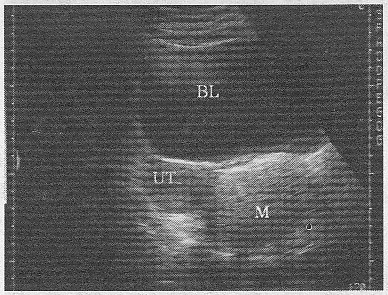

4.如圖,女,26歲,無(wú)明顯不適,盆腔橫斷面,最可能的診斷是

正確答案:C 解題思路:附件區(qū)見(jiàn)無(wú)回聲暗區(qū),這界清晰,其內(nèi)見(jiàn)強(qiáng)回聲水平分界線,在線上方為脂質(zhì)成分,呈均勻密集細(xì)小光點(diǎn),水平線下方為無(wú)回聲暗區(qū)。